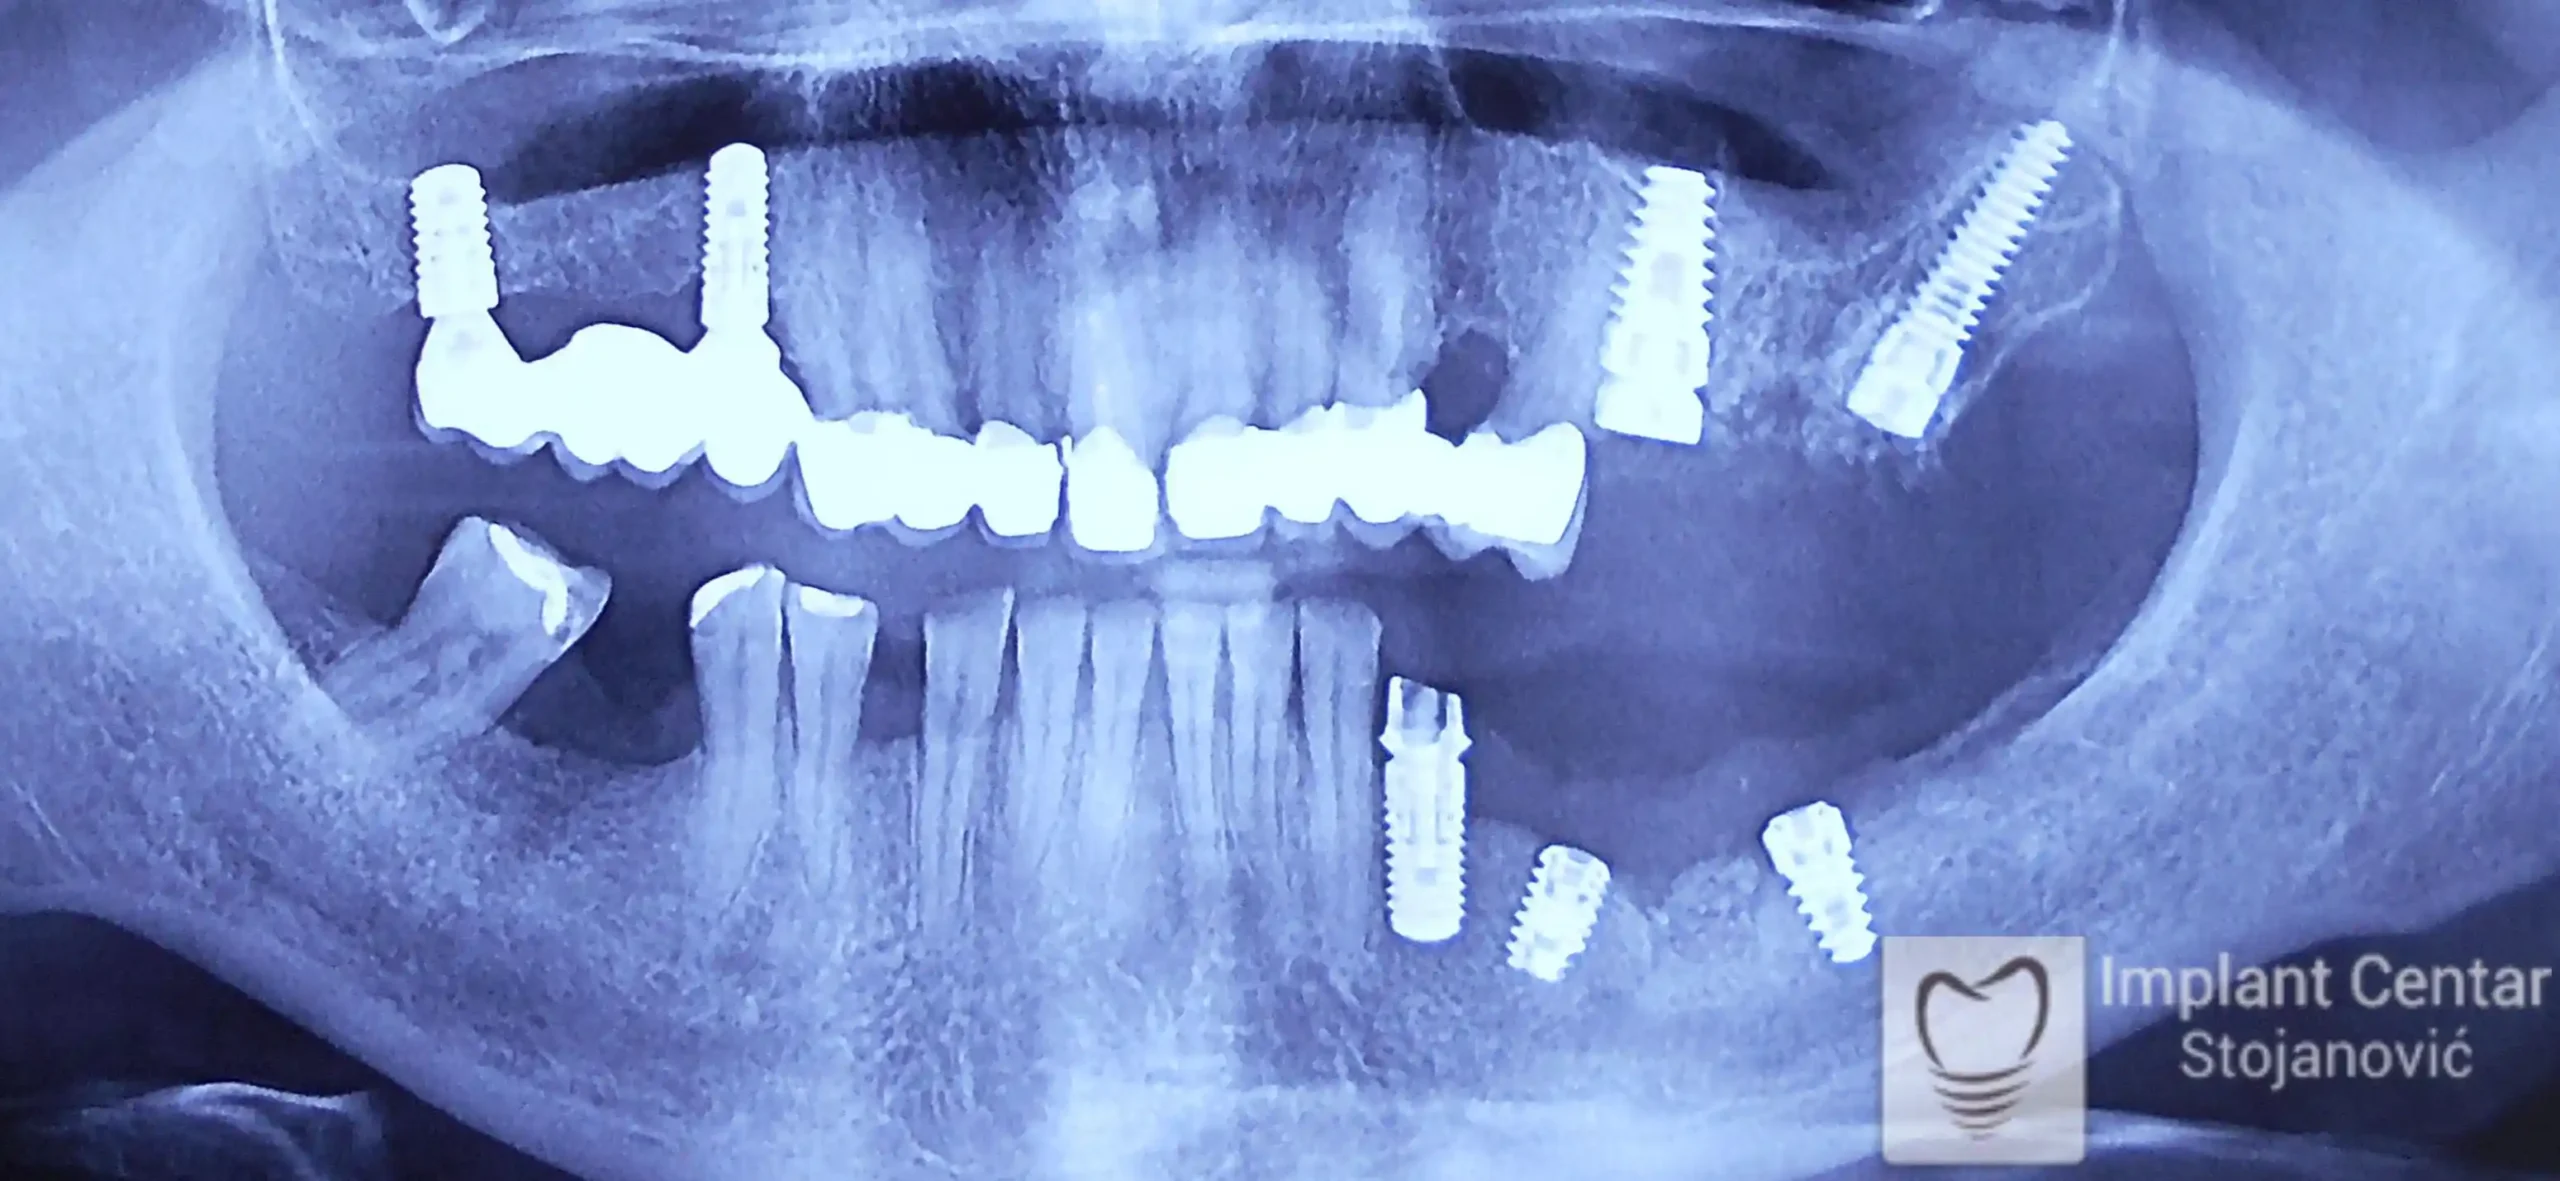

Na slici 1. i slici 2. prikazan je izgled pacijenta pre početka terapije – klinički i rendgenološki.

Nakon vađenja zuba, ugrađeni su implantati. Na slici 3 prikazan je ortopan snimak sa ugrđenim implantatima. Tokom perioda osteointegracije, pacijent je bio zbrinut fiksnim privremenim krunicama na implantatima, koje su izrađene samo dva dana nakon hirurške intervencije.